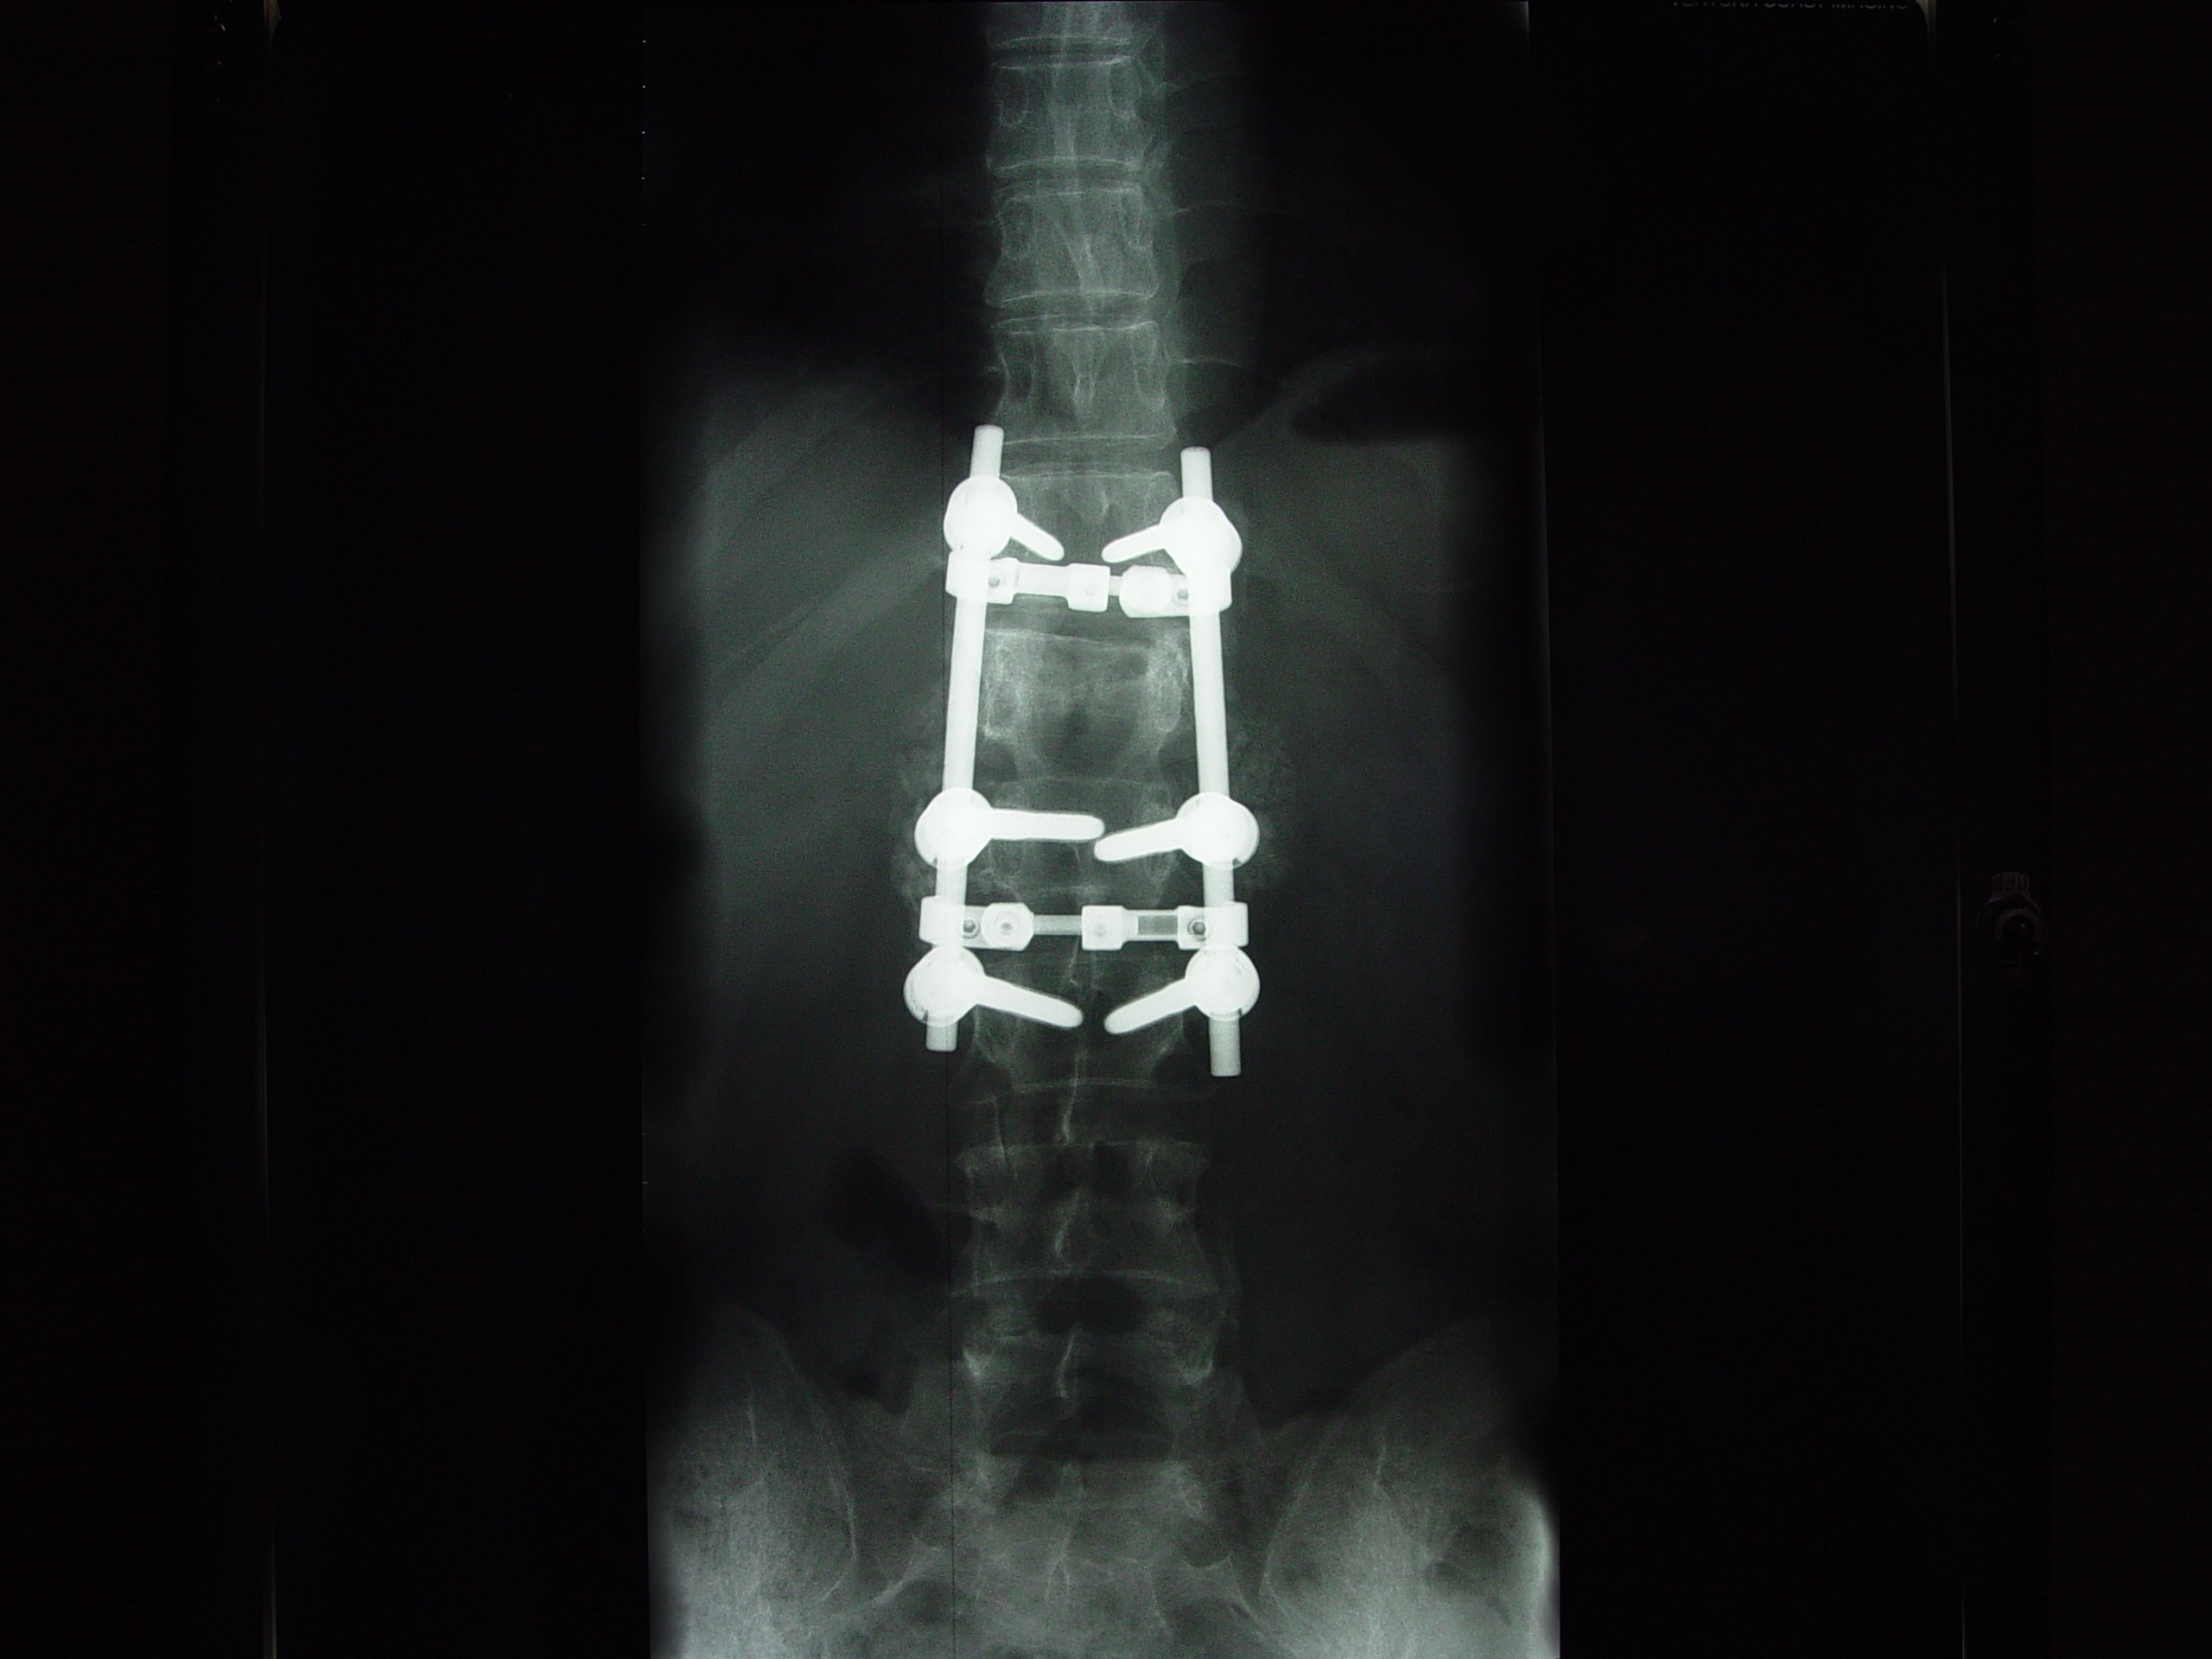

He has TWO rods in his back for support up and down... Two screws at the bottom of each rod and one at the top... He is in recovery at this time more than likely still...

He Faces a LONG three to Four months of bed rest while his back heals up... The Best of luck in all of this. The Doctors were able to do ALL of the surgery through his THIN little body Via his BACK and Did not have to cut his chest etc at all... He has 2 rods in his back and that is NOW confirmed and what I posted last night late is all good...

The hardware is coming out! On April 28th I'm gettin' this monkey off (out of) my back. Hopefully it is the source of the leg pain that has slowed the recovery process.

DSC09486.JPG

The Monkey